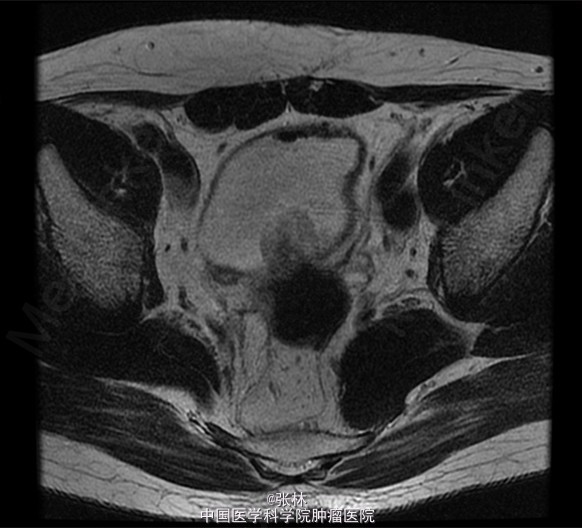

CT:膀胱充盈尚可,内见积气、气液平面;膀胱后壁明显不规则增厚,形成肿物,边界不清,范围约4.8×2.8cm,膀胱壁外缘毛糙,局部与直肠前壁分界不清。考虑:膀胱后壁肿物,与直肠关系密切,考虑为恶性。 MR:膀胱左后壁肿物,与精囊腺及后方直肠分界不清,膀胱充盈状态不同,形态较前改变,现范围约3.6×4.2cm,边界不清楚,T1WI呈低信号,T2/FS呈高信号,DWI扩散受限,增强扫描呈明显不均匀强化,考虑为恶性。